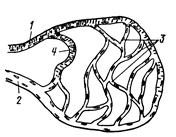

Рис. 200. Схема проводящей системы сердца:

1 — синусно-предсердный узел; 2 — предсердно-желудочковый узел; 3 — предсердно-желудочковый ствол (пучок Гиса); 4 — его ножки и разветвления.